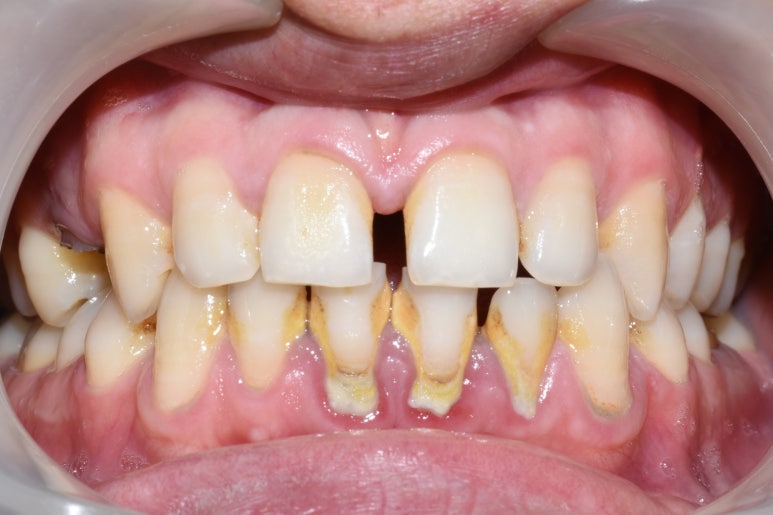

아래 두 사진은 이 환자가 저희 치과에서 스케일링을 받고 난 전 후 사진입니다.

광화문 가까운 연세예감 치과 스케일링 전후사진

치석이 아주 많이 쌓인 모습. 잇몸도 부어있습니다.

20대초의 나이임에도 불구하고 구강관리가 잘 되지않고 치석이 많이 쌓인 모습, 잇몸도 전반적으로 붉은 모습을 볼 수 있습니다.